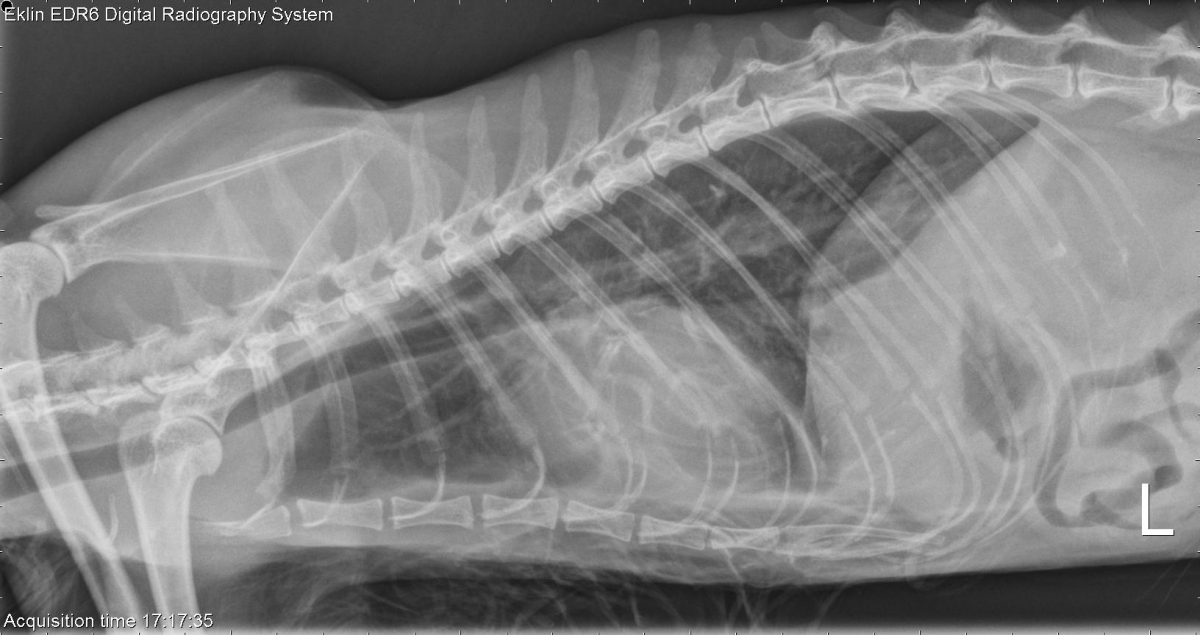

Today’s case is a 12-year-old female neutered domestic short hair cat with intermittent pyrexia and vomiting. What are your findings?

R LAT Thorax

L LAT Thorax

DV Thorax

VD Thorax

There is moderate wet hair coat artifact on the body wall. The cardiac silhouette is enlarged and moderately rounded. There is increased opacity in the pleural space with retraction of the lung lobes and pleural fissure lines. The pulmonary vasculature is mildly enlarged. There is an increased interstitial pattern in the right caudal lung lobe on the ventrodorsal projection. The peritoneal detail is poor.

Cardiomegaly – pericardial effusion, cardiomyopathy, hypervolemia

Pleural effusion – Transudate, exudate, chyle, hemorrhage

There was significant pericardial effusion on echocardiography. The spleen aspirates showed suspicion of lymphoma. Further workup was not pursued.